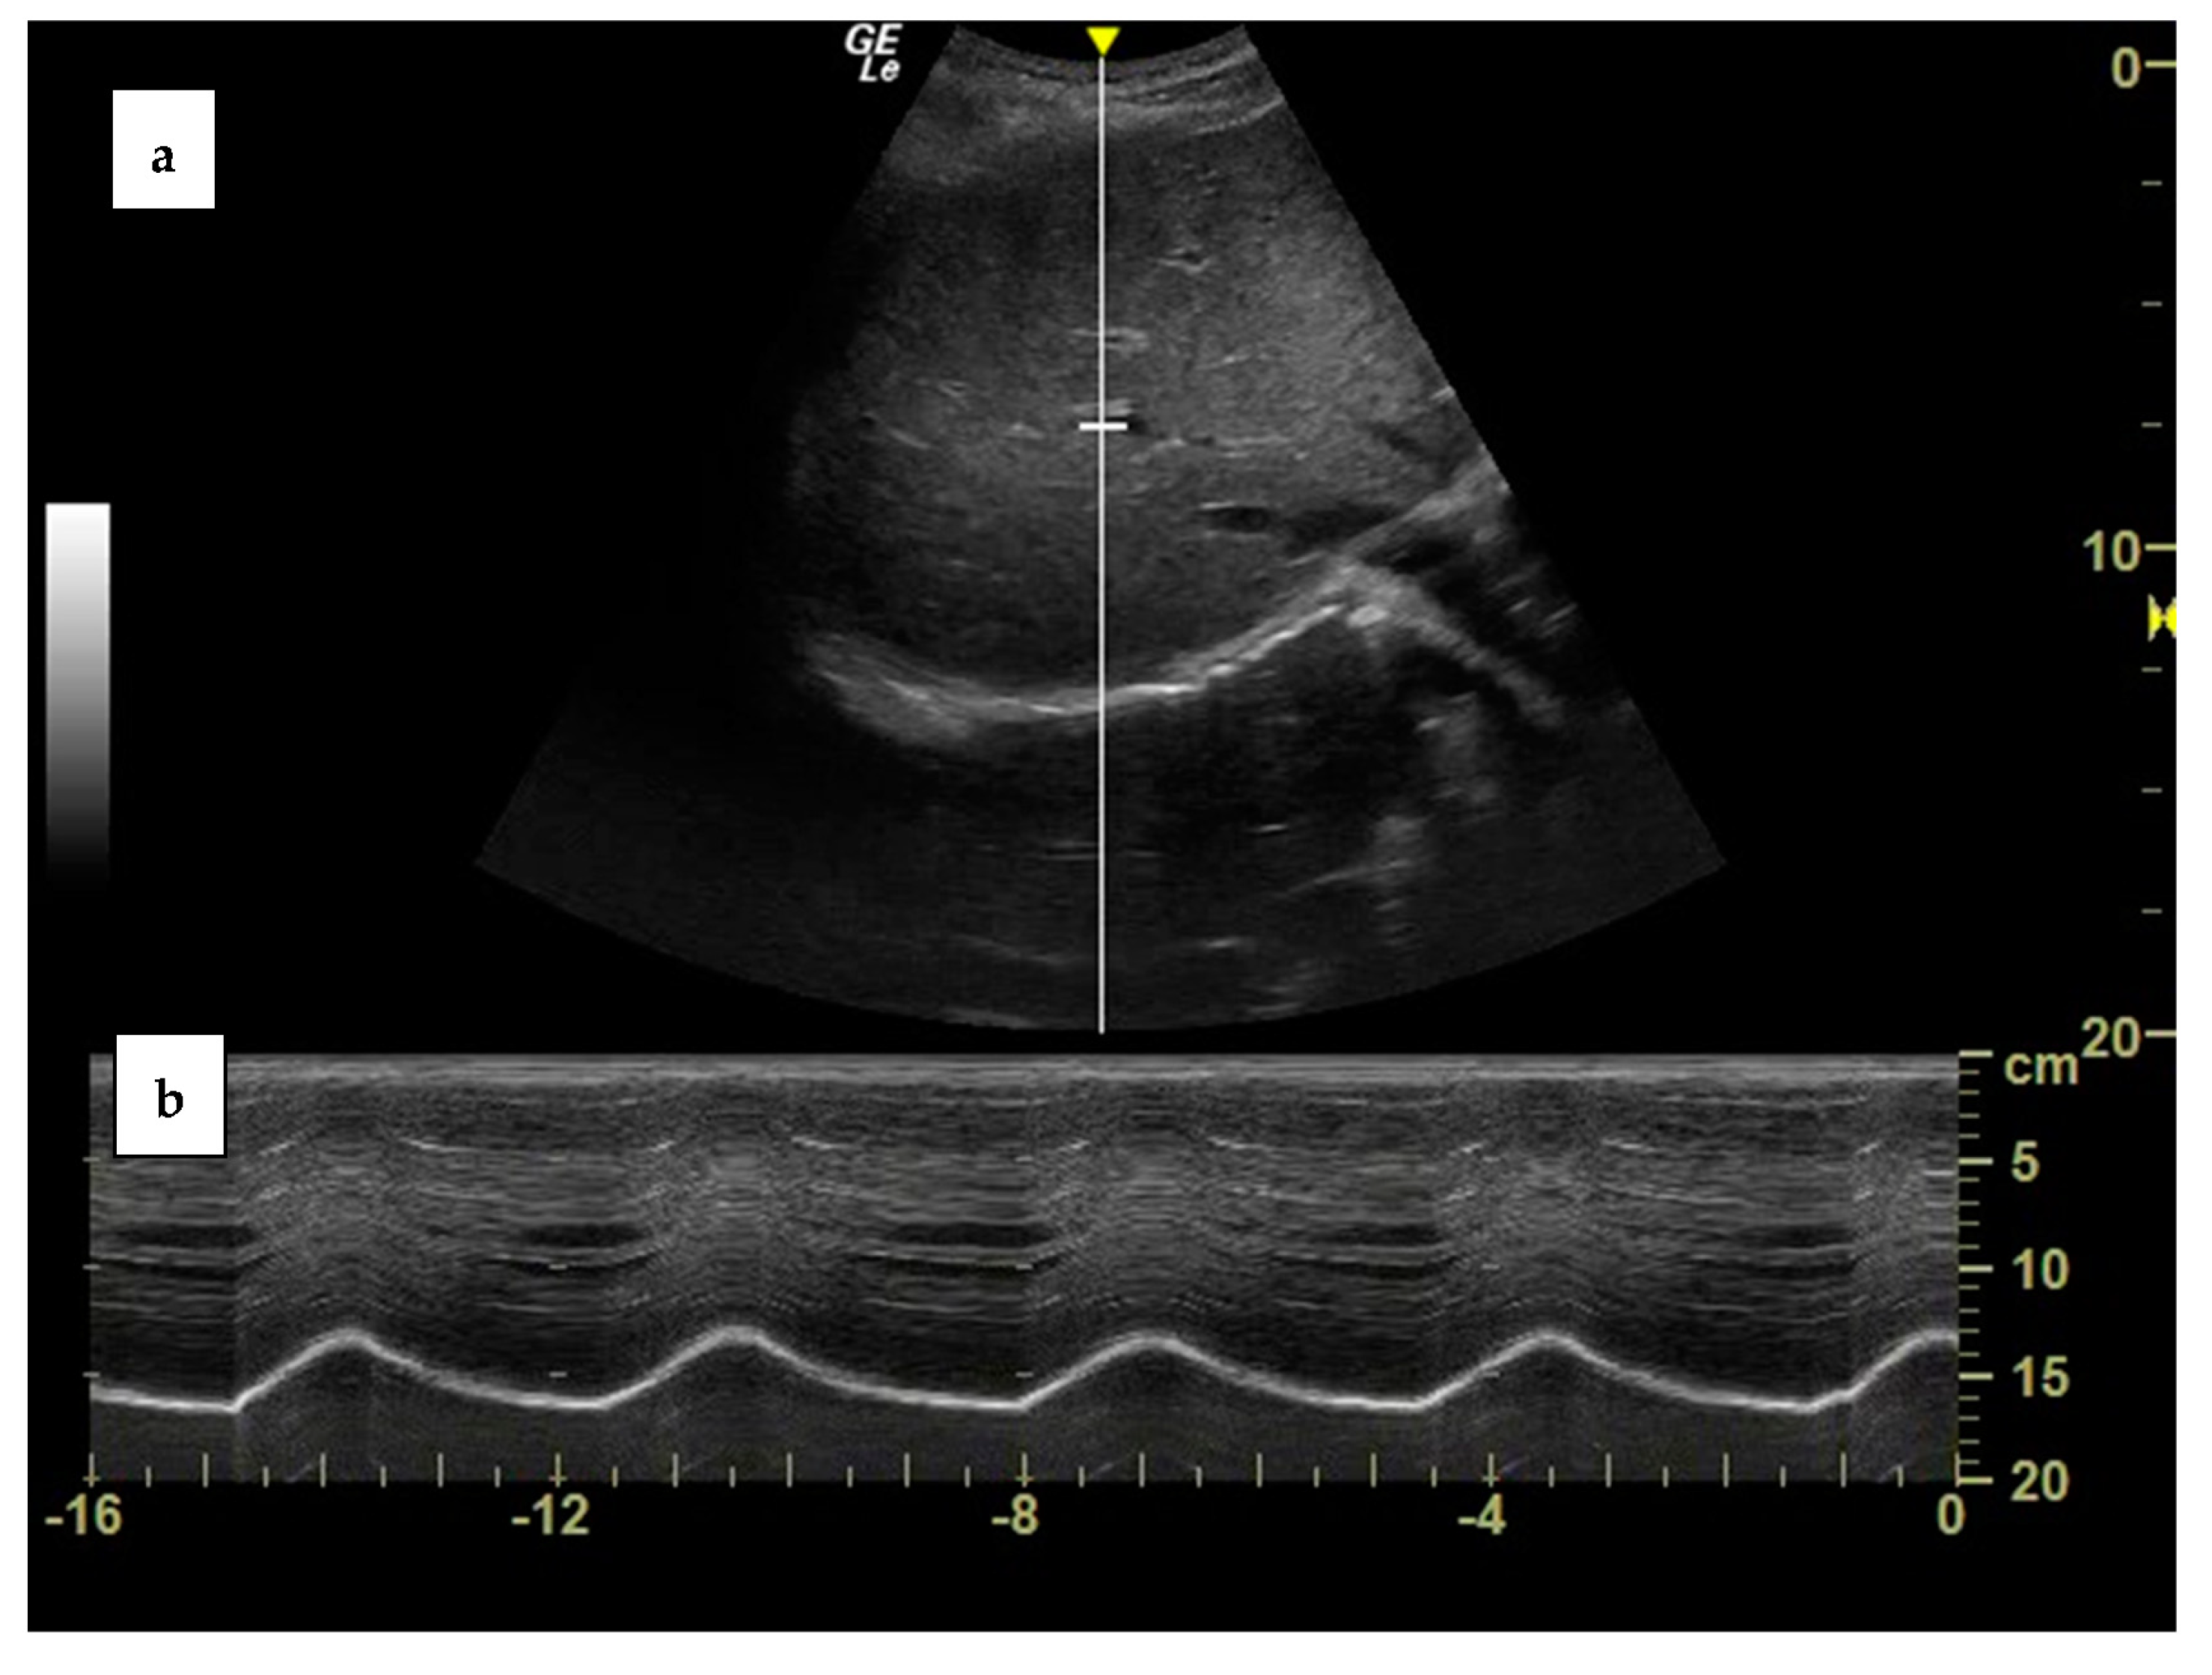

Assessment of the right hemi diaphragm motion from the subcostal view Diaphragm Function Using Ultrasound Ultrasound evaluation of diaphragm function in mechanically ventilated patients: This chapter focuses on thoracic ultrasound as a noninvasive technique for diaphragm morphological and functional. Comparison to phrenic stimulation and prognostic implications Functional imaging with fluoroscopy (or ultrasonography or magnetic resonance imaging) is a simple and effective method of diagnosing diaphragmatic. The main goals of diaphragm ultrasound in critically ill patients. Diaphragm Function Using Ultrasound.

Diaphragmatic excursion measured by an ultrasound system. (A) Tidal Diaphragm Function Using Ultrasound Comparison to phrenic stimulation and prognostic implications The main goals of diaphragm ultrasound in critically ill patients are: Assessment of diaphragm function over time:. Functional imaging with fluoroscopy (or ultrasonography or magnetic resonance imaging) is a simple and effective method of diagnosing diaphragmatic. This chapter focuses on thoracic ultrasound as a noninvasive technique for diaphragm morphological and functional. Ultrasound measurements. Diaphragm Function Using Ultrasound.

MMode Ultrasound Assessment Of Diaphragm Movement RK.MD Diaphragm Function Using Ultrasound This chapter focuses on thoracic ultrasound as a noninvasive technique for diaphragm morphological and functional. Ultrasound evaluation of diaphragm function in mechanically ventilated patients: Ultrasound measurements of diaphragm thickness have been used to identify diaphragm atrophy. The main goals of diaphragm ultrasound in critically ill patients are: Comparison to phrenic stimulation and prognostic implications Assessment of diaphragm function over time:.. Diaphragm Function Using Ultrasound.